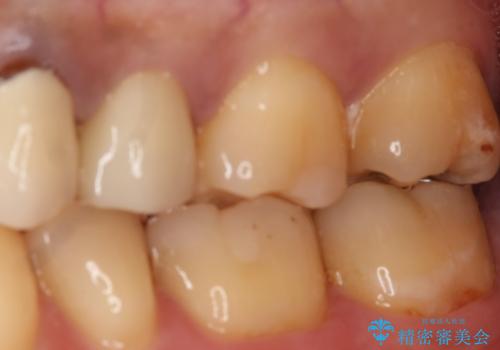

- 左上7番の銀歯のやり変えを希望された患者様です。

セラミックでの治療を希望されたため切削量などを考慮し、セラミックインレーでの治療を計画しました。

銀歯を除去し形態を整えたのち、印象しています。